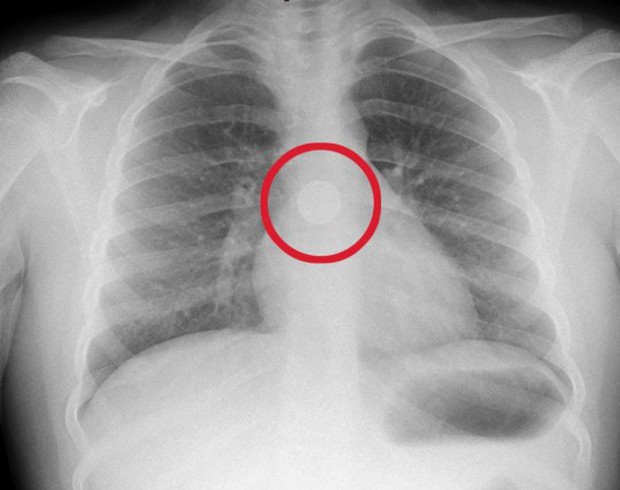

Bác sĩ nhanh chóng tiến hành chụp X-quang để xác định vấn đề. Lý do khiến Sarah lâm vào tình cảnh nguy kịch là vì bên trong thực quản em có một dị vật và nó đang cháy âm ỉ bên trong. Lúc này, cô bé đang bị nghẹt thở vì dị vật chặn đường hô hấp. Với sự trợ giúp và hướng dẫn của bác sĩ, Sarah đã ho mạnh và đẩy dị vật rơi ra ngoài.

Ảnh chụp X-quang thực quản của cô bé